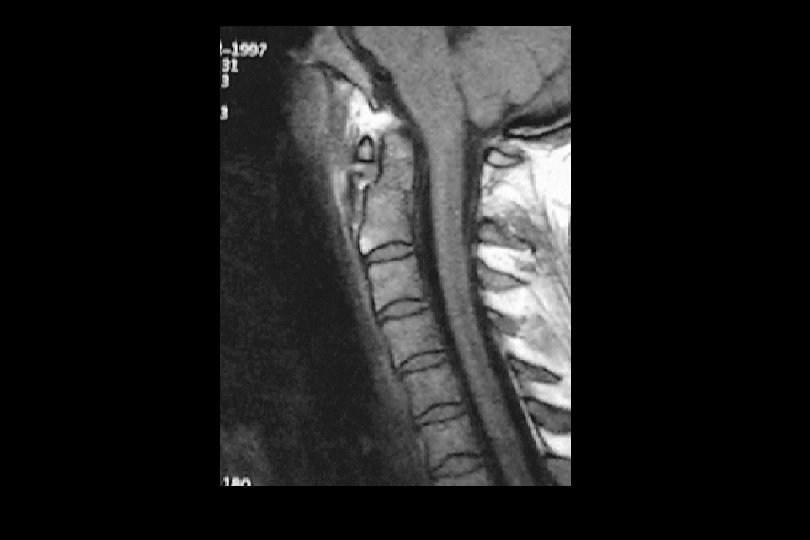

Ekstrensek patolojiler • • Epidural hematom Kemik parçacıkları Dislokasyon Akut disk herniasyonu

İntrensek patolojiler • • Subdural hematom Subaraknoidal kanama Omurilik kontüzyonu Omurilik ödemi Omurilik kesisi Hematomiyeli Dura yırtığı Kök kopması